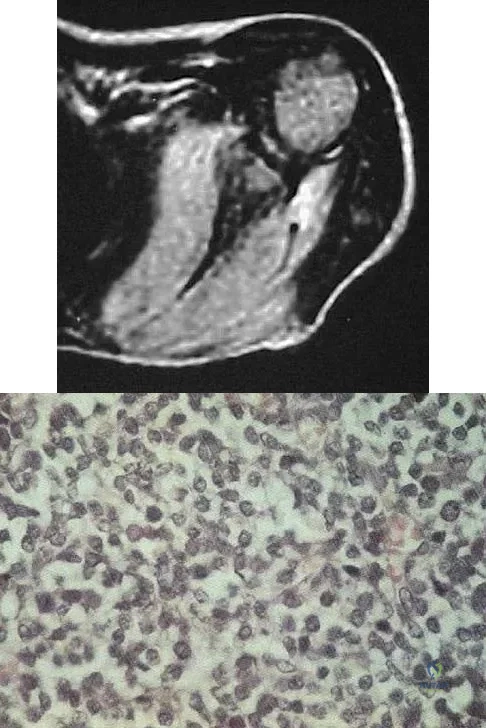

A 16-year-old girl has had pain in the left groin for the past 4 months. She notes that the pain is worse at night; however, she denies any history of trauma and has no constitutional symptoms. There is no history of steroid or alcohol use. Examination reveals pain in the left groin with rotation of the hip. There is no associated soft-tissue mass. A radiograph and MRI scan are shown in Figures 32a and 32b, and biopsy specimens are shown in Figures 32c and 32d. What is the most likely diagnosis?

Explanation